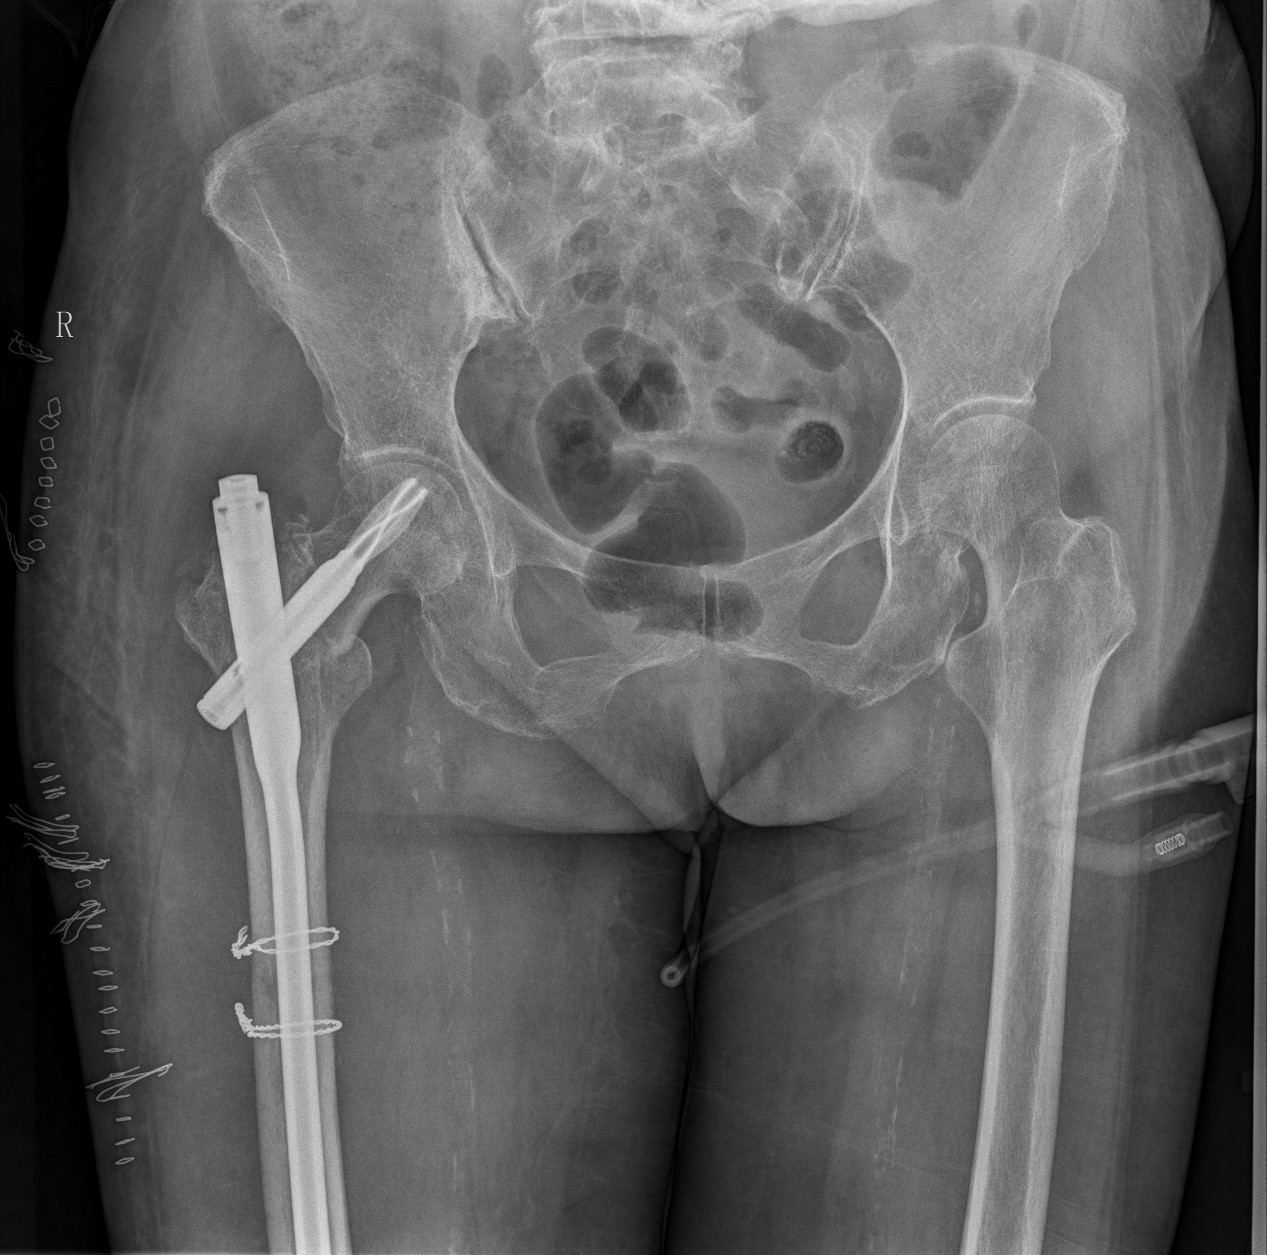

案例二:51岁男性意外摔伤

患者情况:吴先生因路面湿滑不慎摔倒,导致右髋部疼痛并活动受限,经检查确诊为股骨粗隆间骨折。

治疗难点:

1.骨折部位解剖重建的准确性;

2.内固定材料的选择及固定强度的保障。